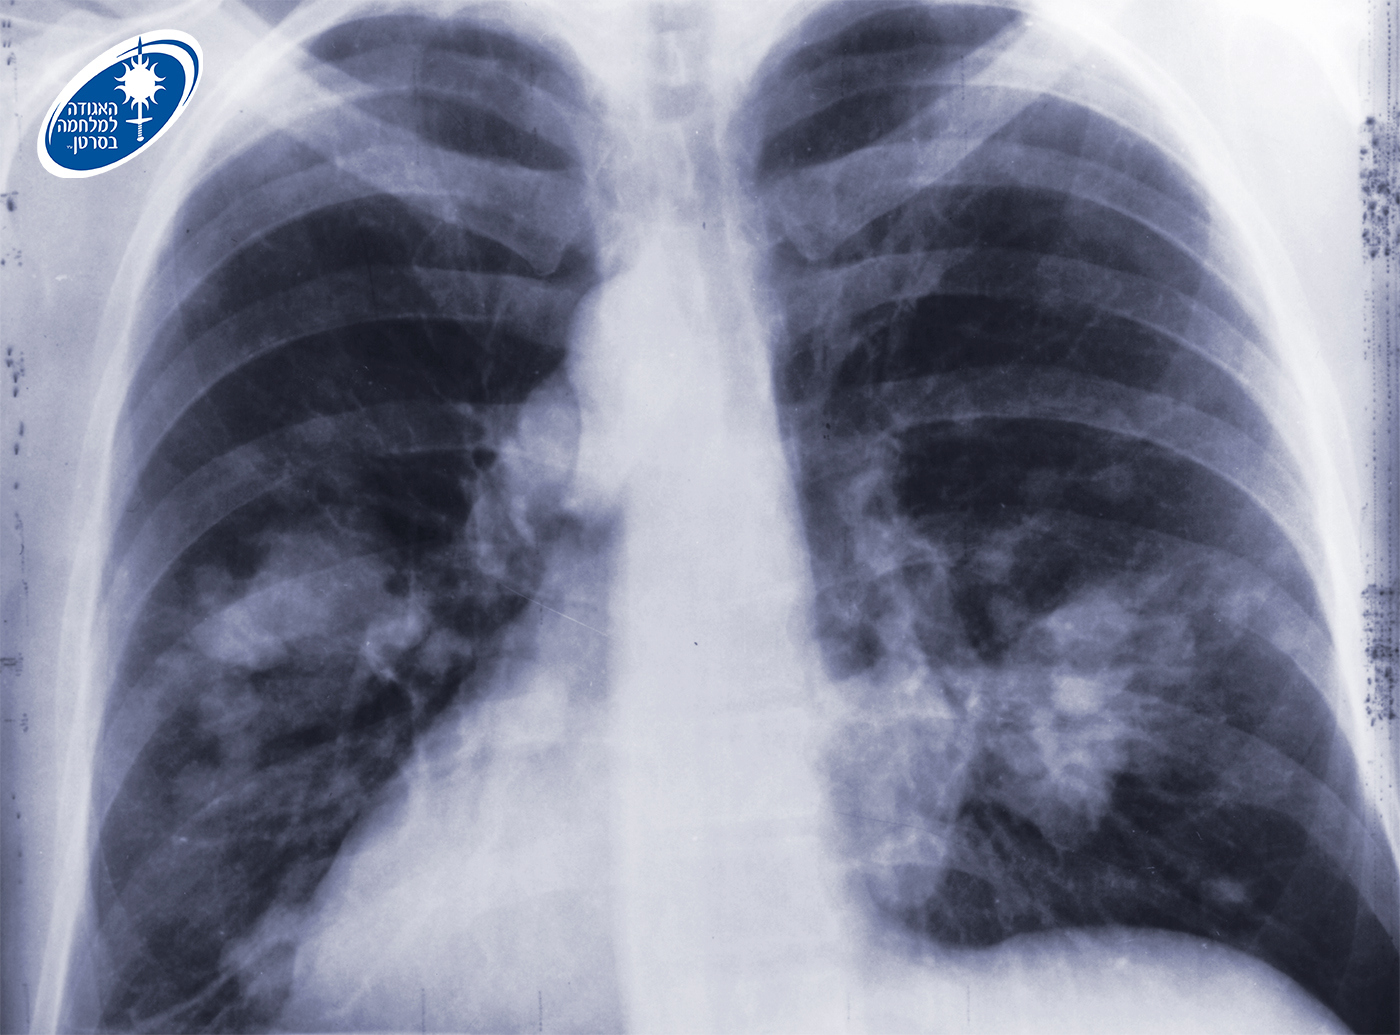

לרגל חודש המודעות הבין-לאומי לקידום המאבק בסרטן הריאה המצוין בחודש נובמבר, האגודה למלחמה בסרטן מגישה נתונים חדשים ומחקרים מדעיים מהם עולה הקשר העקבי בין חשיפה לעישון פסיבי והסיכון לחלות בסרטן הריאה, במיוחד בקרב ילדים. באגודה מדגישים כי ניתן לגלות את סרטן הריאה בשלב מוקדם ומציל חיים וקוראים למעשנים להיבדק.

על פי הערכת האגודה למלחמה בסרטן, עד סוף שנת 2025 יאובחנו בישראל כ-2,800 נשים וגברים עם סרטן הריאה, וכ-1,800 ככל הנראה ימותו מהמחלה. מכלל סוגי הסרטן, סרטן הריאה אחראי לעיקר התמותה בקרב גברים יהודים וערבים בישראל, ורוב מקרי התחלואה בו מקושרים לעישון אקטיבי וגם עישון פסיבי וניתנים למניעה על ידי הפחתת שיעורי העישון.

באגודה מעדכנים כי ניתן לגלות סרטן ריאה בשלב מוקדם ומציל חיים. כ-80% מהמקרים של סרטן זה קשורים בעישון, ולכן למעשנים כבדים בהווה או בעבר מומלץ לבצע מגיל 50, בדיקת CT במינון נמוך לגילוי מוקדם של סרטן הריאות. הבדיקה נכנסה לסל הבריאות ב-2025 לאנשים בני 75-64 עם היסטוריה של 20 שנות קופסה ומעלה, אם הם מעשנים בפועל או אם הפסיקו לעשן ב-15 השנים האחרונות.